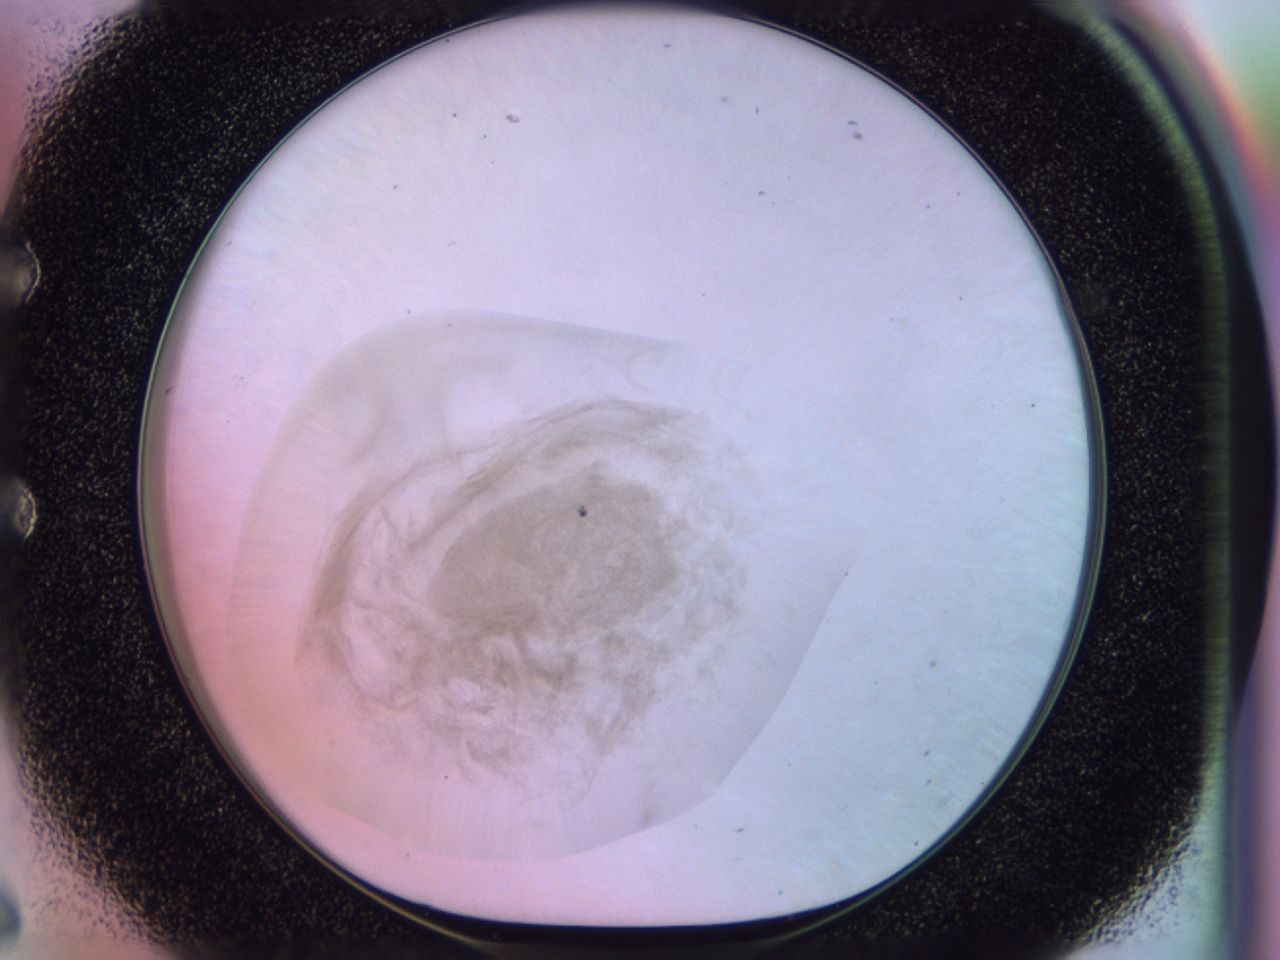

Image 2198

Score

Precipitate

Organization

GSK

00pj_E6_ImagerDefaults_3.jpg